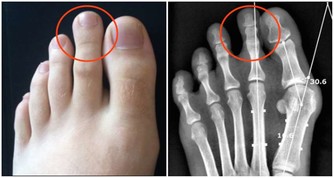

2.排便不暢引發昏厥除了病理性原因,一般人不會刻意憋便,臨床醫學碩士大侖丁說:「糞便積存在腸道裏過久確實會產生一些問題。積存在腸道的糞便會隨著水分被不斷吸收而變得愈發乾硬,導致排便費力,這在患有心血管疾病的患者身上是非常危險的,因為突然增加的腹壓和交感神經興奮可能會導致阿斯綜合徵,即心源性暈厥。」

對患有心腦血管病的人來說,用力排便可能誘發心肌梗死或腦卒中,最好選擇坐便,排完起身要緩慢。